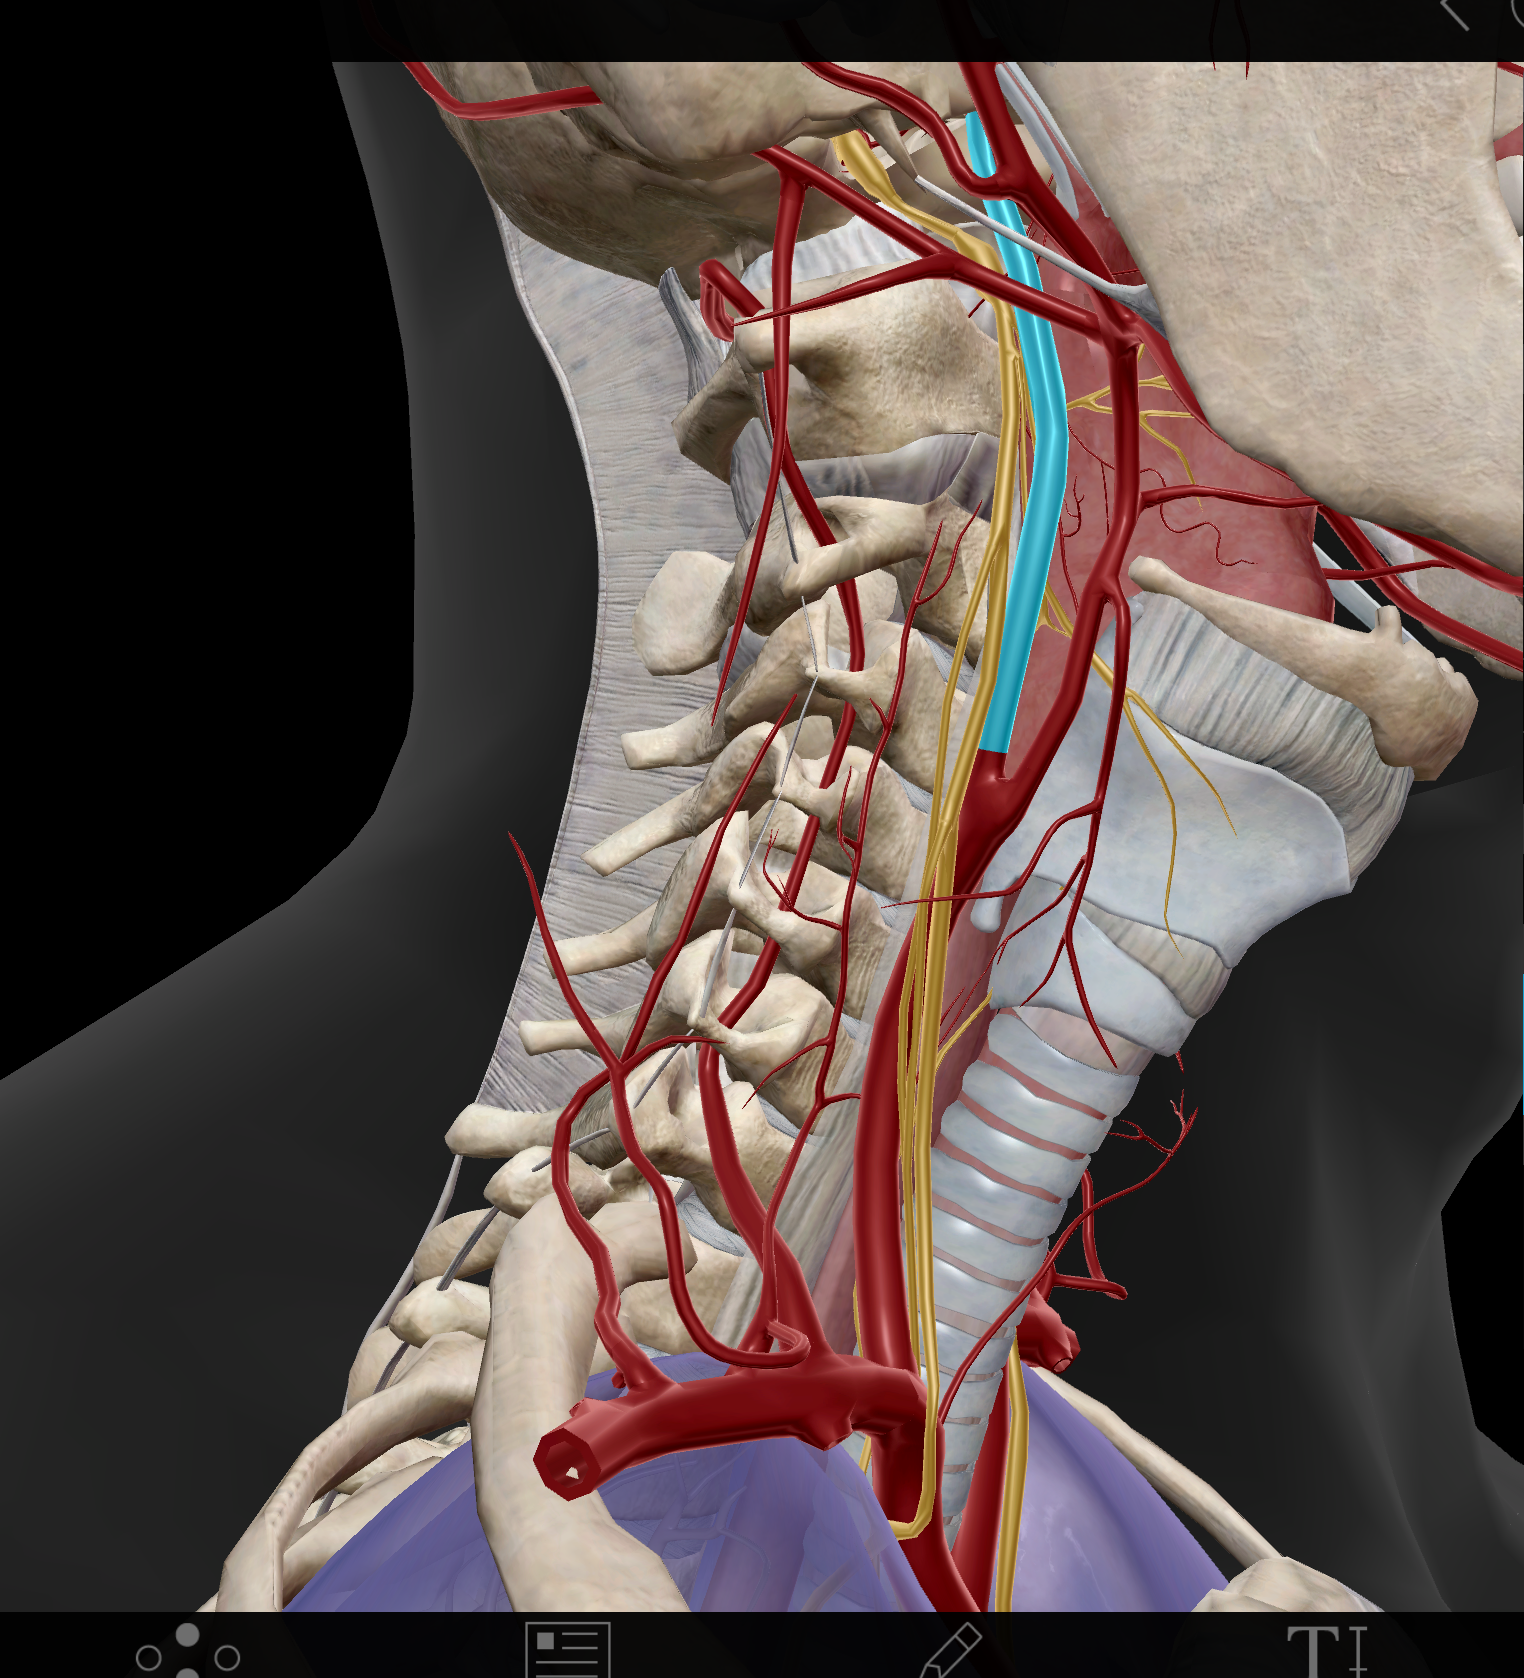

Common carotid a.(L and R)

External carotid a. (L and R)

Internal carotid a. (L and R)